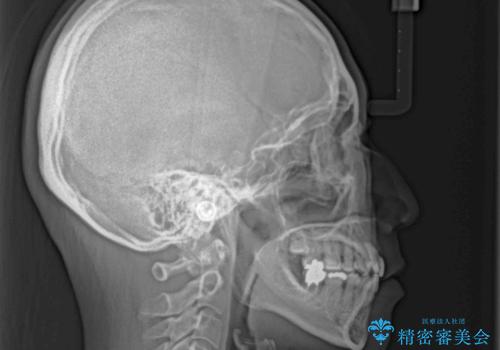

上下前歯が著しく前突している状態であったので、上下左右の小臼歯4本を抜歯し、ワイヤー装置にて矯正治療を行うこととしました。

上顎左側は第二小臼歯に大きなむし歯があったため、通常は第一小臼歯を抜歯するところ、イレギュラーに第二小臼歯を抜歯することとしました。

第二小臼歯抜歯はイレギュラーな治療となるため、アンカースクリューを補助的に使用して、スムーズに治療を行えるように工夫をしました。